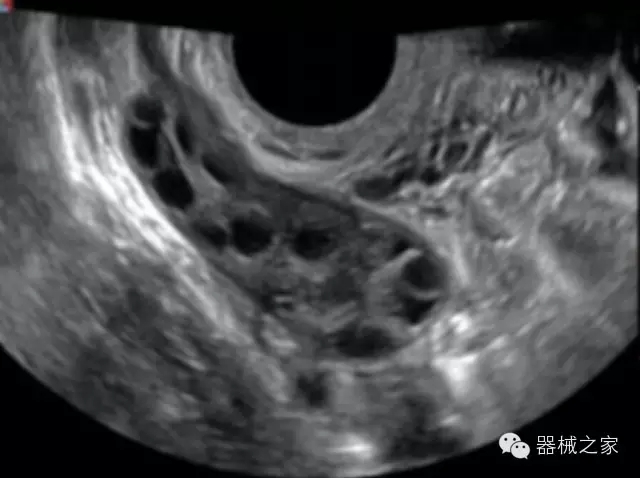

·完整的3D/4D臨床應(yīng)用,STIC, MCUT 和Auto NT等滿足產(chǎn)科所有應(yīng)用;

·更高的HQ羊膜腔鏡成像技術(shù)精細(xì)觀察每一個暗區(qū)細(xì)節(jié);

·高效3D/4D成像技術(shù):高速的4D幀頻,豐富的3D成像模式,智能斷層切片功能;

·獨有的大角度及實時溫控技術(shù),能同一切面顯示宮頸及宮體,有效減低了患者的痛苦,及保護(hù)粘膜保證了醫(yī)療安全;